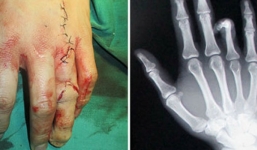

Ghép ngón chân vào bàn tay để... dễ xin việc

17-01-2014 | 19:42